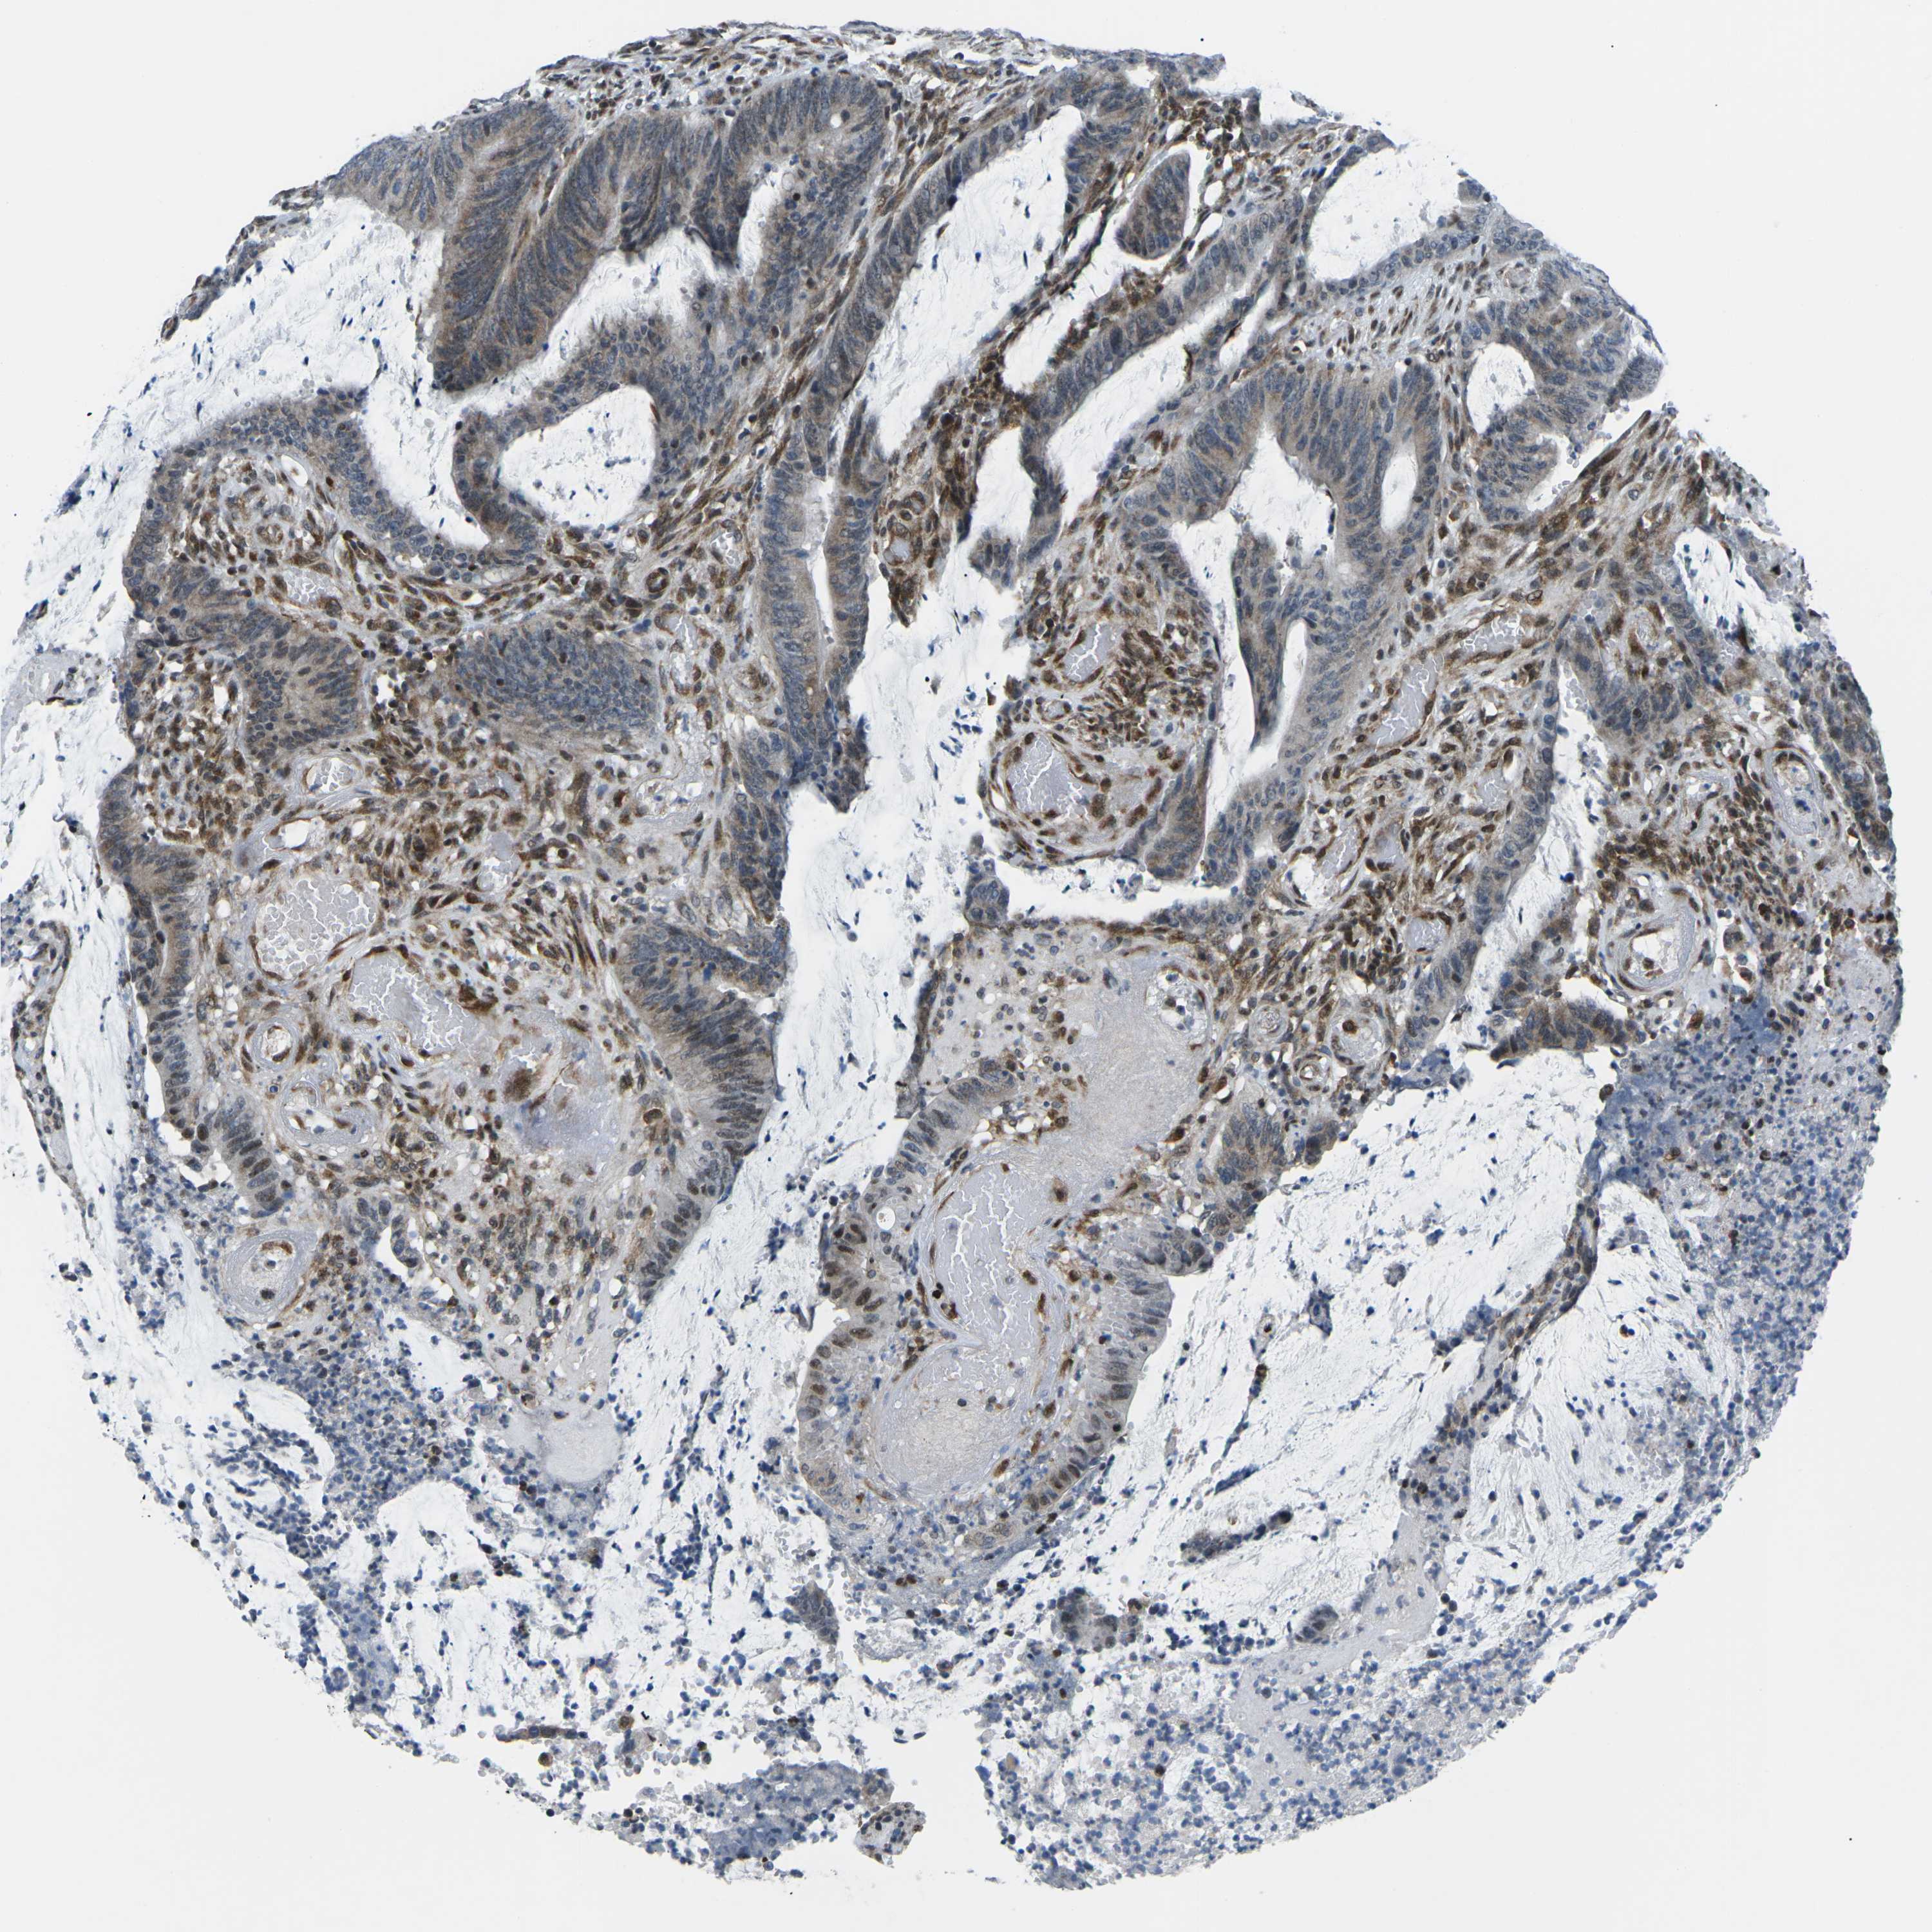

CANCER COLORECTAL CANCER Show tissue menu

Colorectal cancer

Human cancer

Colon adenocarcinoma